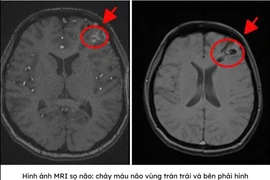

Những cơn đau đầu tưởng chừng “bình thường” ở người trẻ đôi khi lại là tín hiệu của tổn thương mạch máu não cực kỳ nguy hiểm.

(khoahocdoisong.vn) - Bệnh nhân H.T.D.H. (29 tuổi, quận Bình Tân, TPHCM) bị xuất huyết não do dị dạng động tĩnh mạch não. Cách đó 6 tháng, ông ngoại của chị H. cũng phải nhập viện cấp cứu vì lý do tương tự.